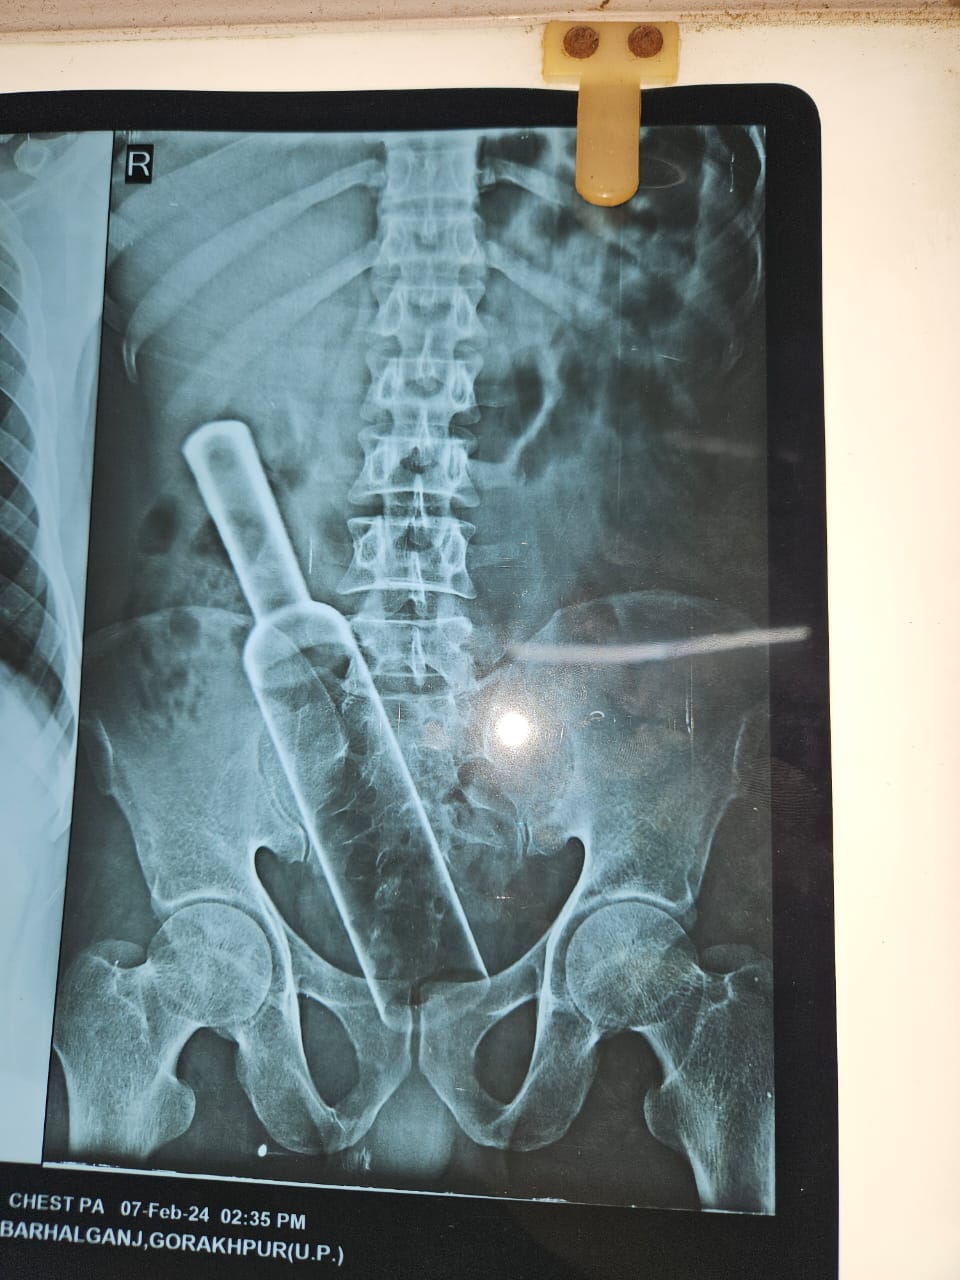

शाही ग्लोबल हॉस्पिटल में एक मरीज़ पेट का दर्द करके आया उसे चेक किया गया तो उसके पेट में लोहे जैसी मजबूत कोई चीज दिख रही थी .जांच करने पर पता चला की लोहे की कोई चीज है जो दो फीट लंबी और 8 सेंटीमीटर चौड़ी है. मरीज से पूछा गया कि यह लोहे की चीज पेट में कैसे गई तो वह ठीक से नहीं बता रहा था. जब आंतों का चेक हुआ तो आंतों के अंदर इतनी बड़ी लोहे की बेलन मिली .चुकी लोहे की बेलन की वजह से संक्रमण काफी फैल रहा था इसलिए इसका इमरजेंसी ऑपरेशन करके लोहे की इस बेलन को बाहर निकल गया .मरिज पूरी कहानी को ठीक से नहीं बता पा रहा था लेकिन यह कह रहा था कि यह गलती से हुआ है. वह बेलन को अपने मल द्वार के रास्ते अंदर धीरे-धीरे डाला जब बेलन पूरा अंदर गया तो बेलन का एक सिर जिसे मुट्ठी कहते हैं वह टूटकर उसके हाथ में रह गया और पूरी बोलन सहित ऊपर वाला सिर( मुट्ठी )पेट के अंदर फस गया ऐसी अजीब गरीब घटनाएं किताबों में पढ़ी जाती हैं लेकिन रियल लाइफ में कम होती है. एक तरह की मानसिक बीमारी है जो सेक्सुअल सेटिस्फेक्शन के लिए किया जाता है कभी-कभी यह अपराध के रूप में भी दूसरों द्वारा किया जाता है .मरीज का नाम उमेश उम्र 32 साल पिता का नाम रमेश ग्राम अस्थवला बेला बीरभान है. मरीज का नाम छिपाया गया है .

इस समय मरिज पूर्ण रूप से ठीक है एक-दो दिन में उसकी छुट्टी कर दी जाएगी.